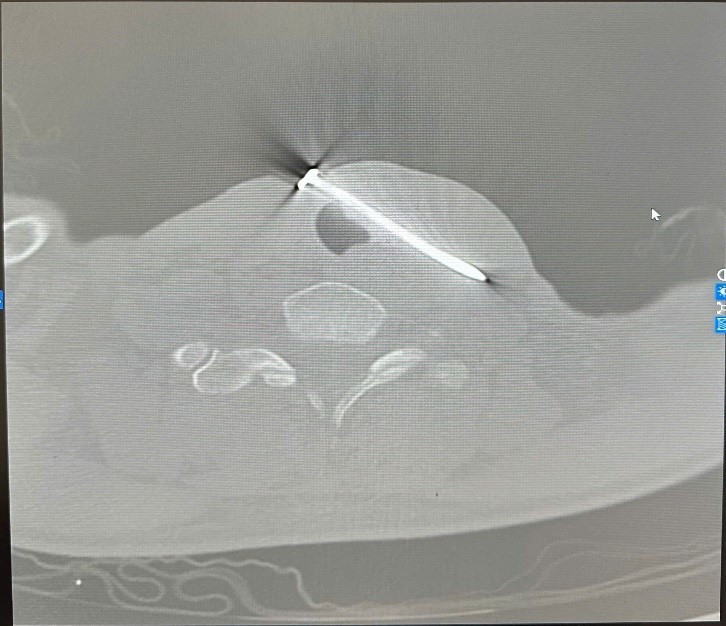

Kết quả cho thấy dị vật xuyên qua thành bên trái khí quản và đường đi của tĩnh mạch cảnh trong trái, một tổn thương cực kỳ nguy hiểm, có nguy cơ gây suy hô hấp cấp, sốc mất máu và tử vong nếu không được can thiệp kịp thời.

xuyen-thau-1-4671.jpg

Hình ảnh đinh sắt trên phim chụp - Ảnh BVCC

Nhận định tình trạng nguy kịch, kíp trực cấp cứu nhanh chóng hội chẩn cùng bác sĩ trực Ngoại Lồng Ngực, sau đó nhanh chóng chuyển bệnh nhân lên phòng mổ. Cuộc phẫu thuật diễn ra khẩn trương, chính xác: các bác sĩ tiến hành rút dị vật, khâu phục hồi khí quản tổn thương và xử trí lỗ thủng tĩnh mạch cảnh trong trái.